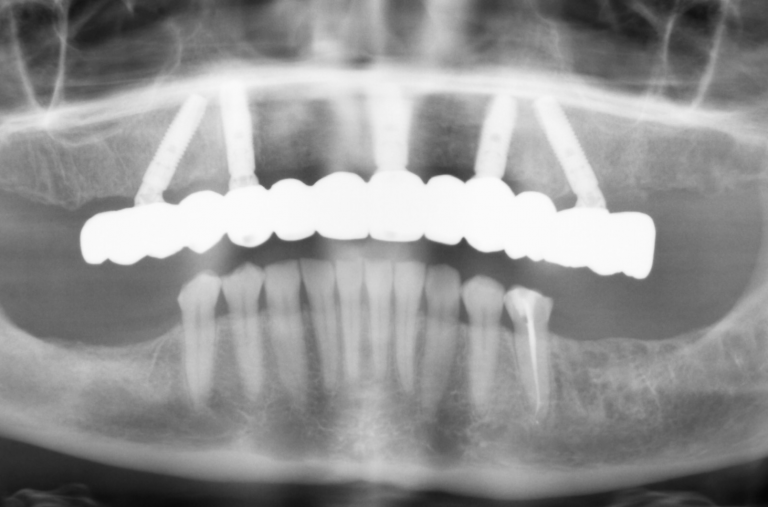

Dental implants can support various prosthetics, depending on the number of teeth that need replacement:

- Implant crown: Ideal for replacing a single missing tooth.

- Implant bridge: Used to replace three to four missing teeth in a row.

- Implant overdenture:: Designed to replace a full arch of teeth, often used for patients who have lost most or all their teeth.

- Implant fixed prosthesis: A permanent solution for a full arch of lost teeth, providing complete restoration.